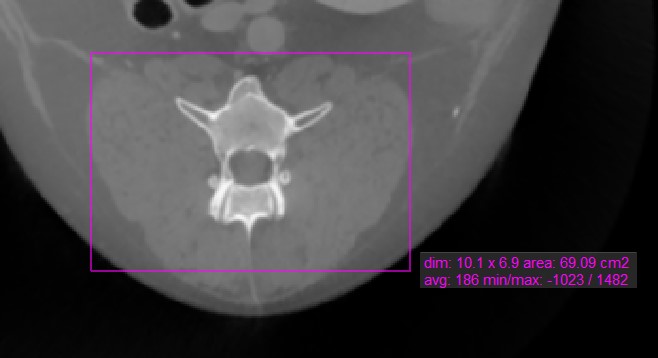

Téglalap mérés¶

A Téglalap mérés eszköz lehetővé teszi a felhasználók számára, hogy téglalap alakú területet jelöljenek az aktív kép egy szeletén.

Válassza ki a Téglalap mérés eszközt, és rendelje hozzá az elérhető egérgombok egyikéhez. Indítsa el a mérést az aktív kép szeletén való kattintással, majd húzza az egeret a téglalap alak eléréséhez. Engedje el az egeret, ha elégedett a kijelölt terület méretével.

Az összes elérhető mérési érték megjelenik a mérés mellett.

A kijelölt terület módosításához mozgassa a téglalap alak négy pontjának egyikét a Alapértelmezett eszközzel.